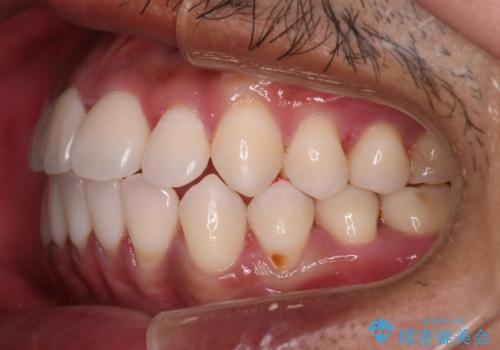

- 全体的に歯並びをよくしたいとのことで来院されました。初診時、患者様はセラミック矯正とワイヤー矯正で迷われていました。

開口(オープンバイト)のため噛み合わせを考慮してワイヤー矯正を提案させていただきました。

IPR(歯と歯の間を削る処置)と顎間ゴムを行い歯並びを整える治療計画を立てました。